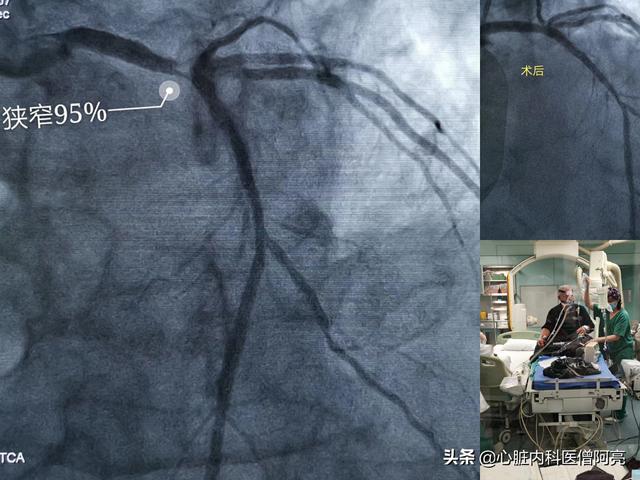

Le travail d'urgence du Dr Cui sur un patient de 80 ans souffrant d'une crise cardiaque aiguë et d'une sténose de 95 % du tronc principal gauche a été effectué avec soin, avec un risque très élevé de mort subite !

Malgré les progrès de l'industrie du stent et des techniques chirurgicales, le taux de resténose du stent est encore de l'ordre de 5 % (contre environ 20 % les années précédentes). Ces patients présentent un risque élevé de resténose et le chirurgien leur demande souvent de passer une imagerie de contrôle 6 à 9 mois ou 1 an après l'intervention.L'objectif est principalement : 1. de clarifier la situation de l'endoprothèse, de déterminer s'il y a prolifération et resténose à l'intérieur de l'endoprothèse ? 2. de déterminer si les lésions critiques restantes non traitées s'aggravent encore, et s'il y a aggravation, de la traiter à temps, afin d'éviter l'infarctus du myocarde, qui n'est pas encore une menace vitale !